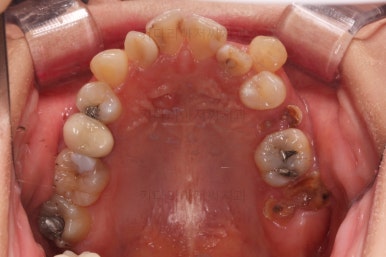

초진 시 입안의 모습입니다.

이미 썩어서 부러진 치아도 몇 개 보이고요.

많이 삐뚤어진 치아쪽은 양치가 힘들어 이미 많이 썩어 있는 상태에 덧니쪽은 잇몸도 많이 내려간 상태였습니다.

말그대로 교정치료 뿐만 아니라 전반적인 치료가 필요한 상황이었습니다.